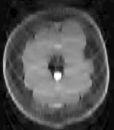

3.4 2D Fast Spin-Echo Brain Imaging of Rapidly Changing Tumor

To examine the performance of our approach with brain MRI data when the assumptions of similarity between consecutive scans is not valid, we used retrospectively acquired data of a patient with GBM. The patient was scanned twice within an interval of five months, and exhibited changes between scans that occupy more than 50% of the brain region. We used T2-weighted FSE sequence (matrix: res = , 36 slices with thickness and no gap, TR/TE=, echo-train length=, flip angle=). We registered the follow-up scan to the baseline scan and examined the results of LACS-MRI (), CS-MRI and TCS-MRI with acceleration factors of 4, 6.4, and 10.6.

Table 3 shows the SNR values for different reconstructions and Figure 6 shows reconstruction results visually, at acceleration factor of 4 (25% of the k-space). In this case, there are major changes between the baseline and the follow-up scans due to therapy response. As a result, TCS-MRI exhibits poor performance in the vicinity of the changing tumor, since it is partially based on similarity between the consecutive scans, an assumption which is not valid in this case.

LACS-MRI, however, convergences to a result which is similar to CS-MRI. This is obtained thanks to the adaptive sampling and the weighting mechanism embedded in LACS-MRI, which reduces the weight given to the similarity to prior scan in the reconstruction process, if such a similarity does not exist.